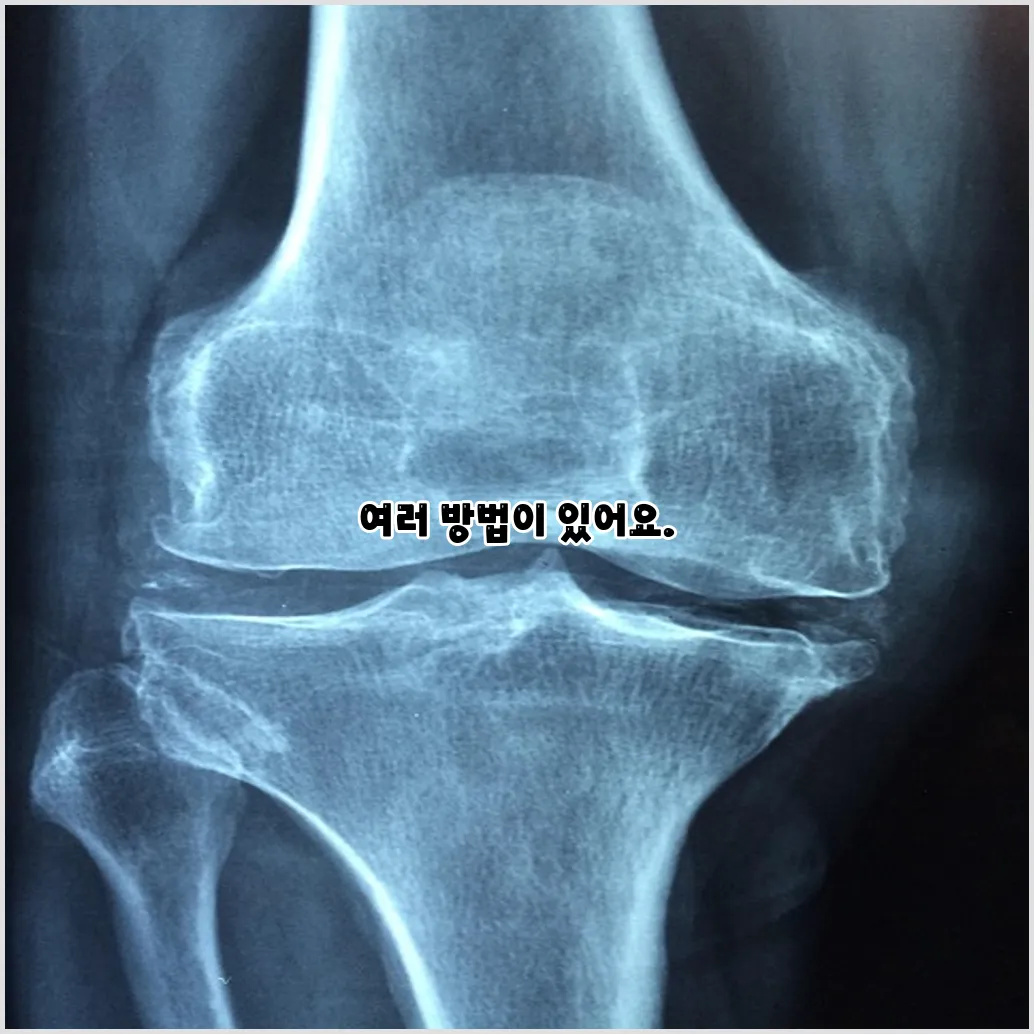

관절염은 일반적으로 두 가지 유형으로 나눌 수 있습니다. 첫 번째는 퇴행성 관절염으로, 노화와 함께 발생하며 관절의 연골이 닳아 없어지는 현상입니다. 두 번째는 류마티스 관절염으로, 면역 시스템의 이상으로 인해 관절이 염증을 일으키는 질환입니다. 이러한 다양한 원인은 통증을 발생하게 하며, 이는 우리의 삶의 질을 떨어뜨릴 수 있습니다.

관절염 통증 완화 방법

관절염 통증을 완화하기 위한 방법에는 여러 가지가 있습니다. 사람마다 다르게 반응할 수 있지만, 여러 접근 방식을 통해 통증을 경감시킬 수 있습니다.